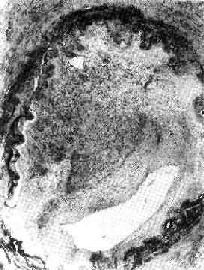

图3-6 机化的血栓

血管腔内的血栓已为肉芽组织取代有再通现象×100